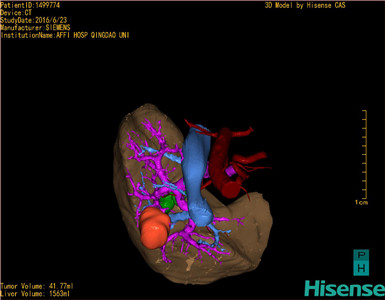

通过调节窗宽窗位调整CT序号,对肿瘤,肝实质,胆囊,下腔静脉,肿瘤,肝动脉、门静脉及肝静脉等进行三维重建;系统自动计算肿瘤体积和肝脏体积。

模拟手术操作,自动计算切除肿瘤体积。肝脏体积为1536ml,肿瘤体积为41.77ml,肿瘤体积为肝脏体积2.7%,通过比60-70岁正常肝脏体积为1262.7±284.31ml,通过术前模拟手术,精准判断切除后剩余肝脏体积能耐受,避免肝衰竭发生。

术前手术方案的规划。

手术顺利,麻醉满意,解剖标本,部分肝呈纤维化,内有灰白色质韧结节,送病理检查。病理检查结果:肝(VIII段)低分化癌伴大片坏死。手术时手术者可开启Hisense CAS系统手势控制功能,对肿瘤的解剖结构进行实时、全方观察、评估,起到术中导航作用。

术前三维重建:

重建图片